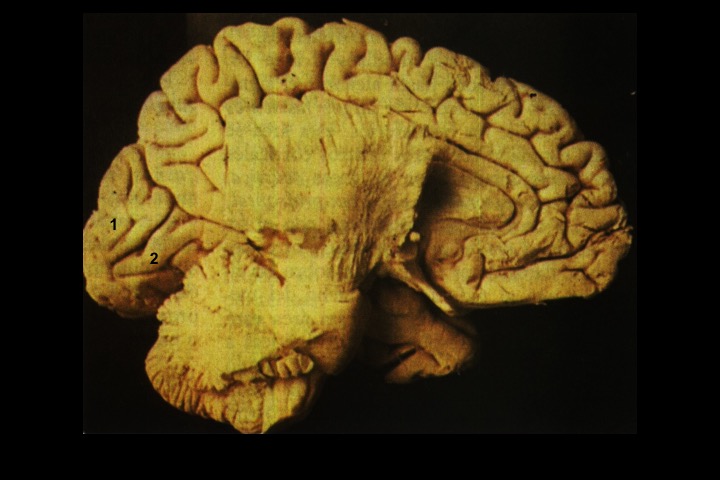

O Prof. Emérito da UFRJ Dr. Adalmir Morterá Dantas está disponibilizando através de nosso website e de nosso canal youtube (cursobom) o Museu de Neuroanatomia, no intuito de promover esta área de conhecimento junto aos estudantes de Medicina.

As figuras são apresentadas em 4 vídeos no youtube e podem ser obtidas via download clicando-se na figura em questão.